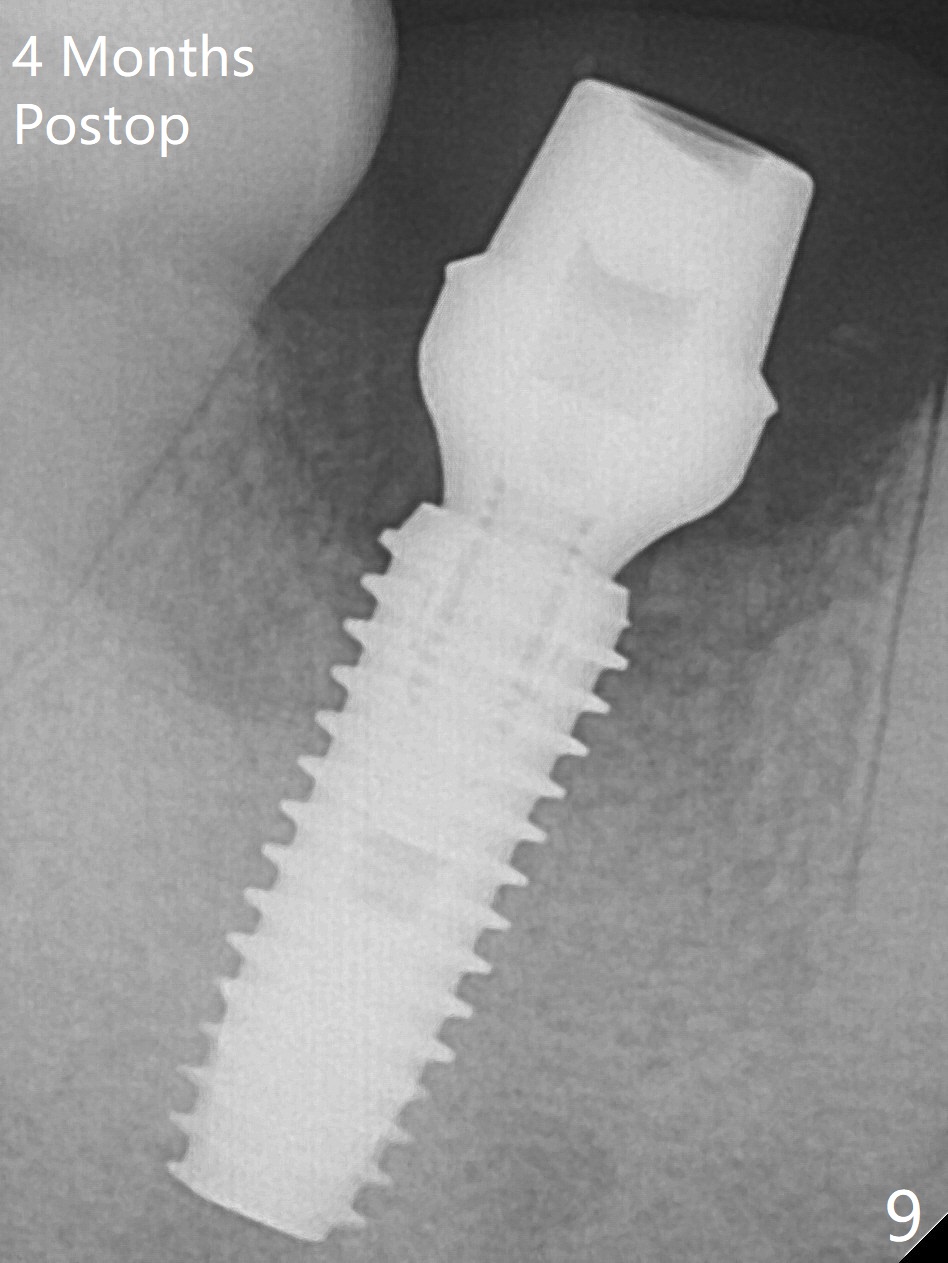

Fortunately no paresthesia is reported postop. Why is the Inferior Alveolar Canal not violated? Fig.7 is a coronal section of CBCT taken for a 40-year-old man at the lower 1st molar (at the septum). At the region, the Canal (brown circle) is close to the lingual plate (L). Because of severe bone loss of the lingual plate of this case (Fig.8 *), osteotomy is intentionally created buccal (green). The deep osteotomy may not contact the Canal, while the hemorrhage may stem from the medullary space (M in Fig.4,7). Bone morphology at the coronal end of the implant apparently changes 4 months postop, suggesting osteointegration (Fig.9). Impression is taken. Bone density around the implant at the crest seems to increase (Fig.10), while there is no soft tissue deficiency 10 months post cementation (Fig.11). The bone appears to regenerate toward the abutment, particularly distally, 14.5 months post cementation (Fig.12). Periimplantitis develops (bleeding on water pik and erythematous and tender buccal gingiva) 1 year 7 months post cementation (Fig.13,14). The 1st three threads are exposed (*). Bone graft with PRF and 6-month membrane or Cytoplast will be needed. Pain disappears 3 days of oral antibiotic. The gingiva looks healthy 1 month later when he returns for bone graft (Fig.15). But the lingual gingival cuff is not so healthy when the crown/abutment is removed (Fig.16 <). Bone graft is not done. For those patients with suboptimal oral hygiene, implants should be placed as low as possible, better with guide for precision.